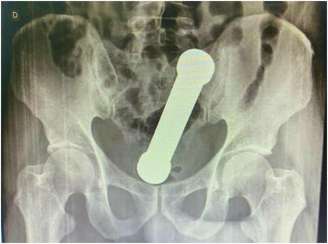

Foto: International Journal of Surgery Case Reports

O caso de um paciente em Manaus (AM) virou artigo científico em uma revista internacional de medicina por se tratar de uma ocorrência bem inusitada. Um homem de 54 anos procurou atendimento médico na capital amazonense com dores no abdômen e dificuldade de evacuar.

Os médicos solicitaram exames para descobrir a origem do problema e se surpreenderam com as imagens de radiografia, que revelaram um halter, aquele peso de mão usado em academias, dentro do corpo do paciente.

O objeto tinha 20 centímetros e dois quilos. Foi necessário um procedimento cirúrgico para anestesiar o homem e poder retirar o halter de seu corpo. A cirurgia foi bem sucedida e o paciente recebeu alta após três dias internado.

O episódio foi descrito na International Journal of Surgery Case Reports com o título ”manejo de incomum corpo estranho retal” e com algumas fotos para ilustrar a excepcionalidade do caso.